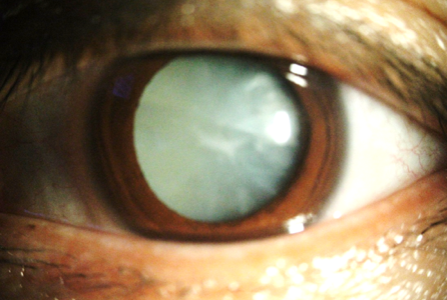

백내장은 홍채와 동공 뒤에 위치한 눈의 자연 수정체가 흐려지는 것을 말합니다. 수정체는 일반적으로 투명하기 때문에 빛이 투과하여 망막에 집중하여 선명한 시력을 얻을 수 있습니다. 백내장이 형성되면 빛이 분산되어 시력이 흐려지거나 어두워집니다. 대부분의 백내장은 시간이 지남에 따라 느리게 발달하지만 독서, 운전 또는 얼굴 인식과 같은 일상 활동에 상당한 영향을 미칠 수 있습니다. 백내장의 가장 흔한 증상은 안개가 낀 창문을 들여다보는 것처럼 흐릿하거나 시야가 흐려지는 것입니다. 피부색도 덜 활기차게 보일 수 있으며, 흰색 이외에도 황갈색 또는 갈색을 띠기도 합니다. 특히 밤에 불빛 주변의 눈부심과 후광은 야간 운전을 어렵게 만드는 또 다른 특징적인 징후입니다. 독서를 위해 더 밝은 조명이 필요하거나 한쪽 눈의 이중 시력으로 어려움을 겪을 수 있습니다. 경우에 따라 처방전 안경이나 콘택트렌즈를 자주 교체해야 한다면 백내장이 진행되는 신호일 수 있습니다. 이러한 증상을 조기에 인지하는 것은 적시에 치료를 받고 삶의 질을 유지하는 데 매우 중요합니다.